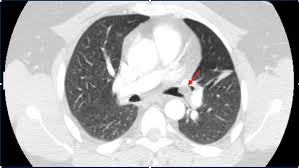

A description of popcorn calcification—meaning images that look like popcorn on a ct. Eccrine angiokeratomatous hamartoma combined with solitary angiokeratoma or verrucous venous malformation: Residents and fellows contest rules | international ophthalmologists contest rules. Endobronchial hamartoma resected by rigid bronchoscope. Report of two cases and comprehensive review of the literature.

A large hamartoma of the spleen. Multiple hamartomas throughout the body occur in cowden's disease. A description of popcorn calcification—meaning images that look like popcorn on a ct. Endobronchial hamartoma resected by rigid bronchoscope. A mass resembling a tumor that represents anomalous development of tissue natural to a part or organ rather than a true tumor. Most isolated hamartomas are benign but in cowden's disease there is a risk that one or more may undergo malignant change.4. High magnification shows the 3 components of fhi. Report of two cases and comprehensive review of the literature.

Hamartoma is a benign (not cancer) growth made up of an abnormal mixture of cells and tissues normally found in the area of the body where the a lesion first described by german pathologist eugen albrecht in 1904, hamartomas are generally benign tumors that may occur in the lungs, skin. A description of popcorn calcification—meaning images that look like popcorn on a ct. The hamartoma can occur in almost any organ and is usually asymptomatic. High magnification shows the 3 components of fhi. In radiology, hamartomas often mimic malignancy. Jump to navigation jump to search. Is that hamartoma is (pathology) a benign mass of disorganized tissue while teratoma is (pathology) a benign or malignant tumour, especially of the gonads, that arises from germ cells and consists of different types of tissue such as skin, hair, or muscle. When located on the skin, especially the face or neck, they can be extremely disfiguring, as.

A description of popcorn calcification—meaning images that look like popcorn on a ct. High magnification shows the 3 components of fhi. A hamartoma is a focal malformation that resembles a neoplasm in the tissue of its origin. The hamartoma is the dark circular object on the left that dominates the image. A large hamartoma of the spleen.